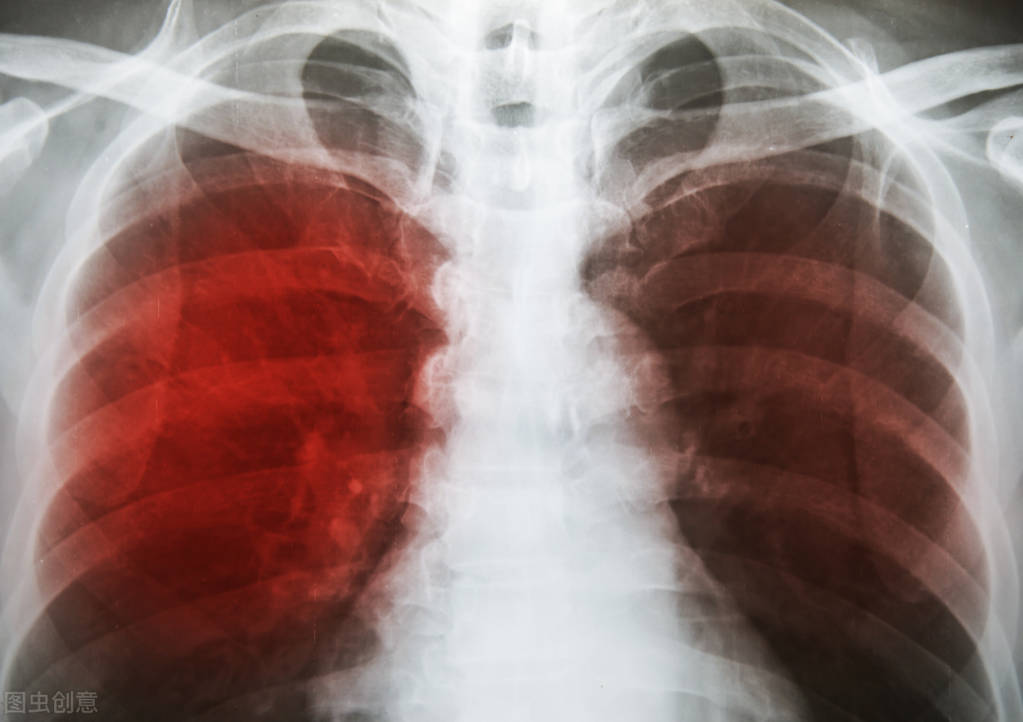

肺炎是一种常见的肺部疾病,根据病因可分为传染性和非传染性两大类。传染性肺炎是由细菌、病毒或真菌等病原体引起的,具有一定的传染性;而非传染性肺炎则通常由环境因素、药物或自身免疫反应引起,不具有传染性。

传染性肺炎的症状包括咳嗽(可能伴有痰液)、发热、寒战、呼吸困难等。对于65岁以上老人、2岁以下儿童以及免疫功能低下者,肺炎可能迅速发展为危及生命的重症。传染性肺炎的传播途径主要是飞沫传播,当患者咳嗽或打喷嚏时,会将含有病原体的飞沫释放到空气中,其他人吸入这些飞沫就可能被感染。

相比之下,非传染性肺炎的症状主要表现为气短和干咳。其原因多样,包括长期接触空气污染物、某些药物的副作用、放射治疗等。虽然非传染性肺炎不具有传染性,但如果未经及时治疗,也可能导致严重的肺部损伤,甚至发展为不可逆的肺纤维化。